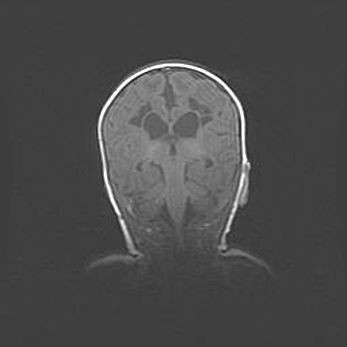

Церебральная ишемия II.

Возраст: 7 дней

Вес: 3350 г

Пол: женский

Окружность головы: 35 см

Срок гестации: 39 недель

Ишемия головного мозга – это состояние, которое развивается в ответ на кислородное голодание вследствие недостаточного мозгового кровообращения. У новорожденных она является следствием дефицита кислорода, что ведет к метаболическим расстройствам различной степени тяжести в тканях головного мозга, в том числе к развитию коагуляционных некрозов и гибели нейронов.